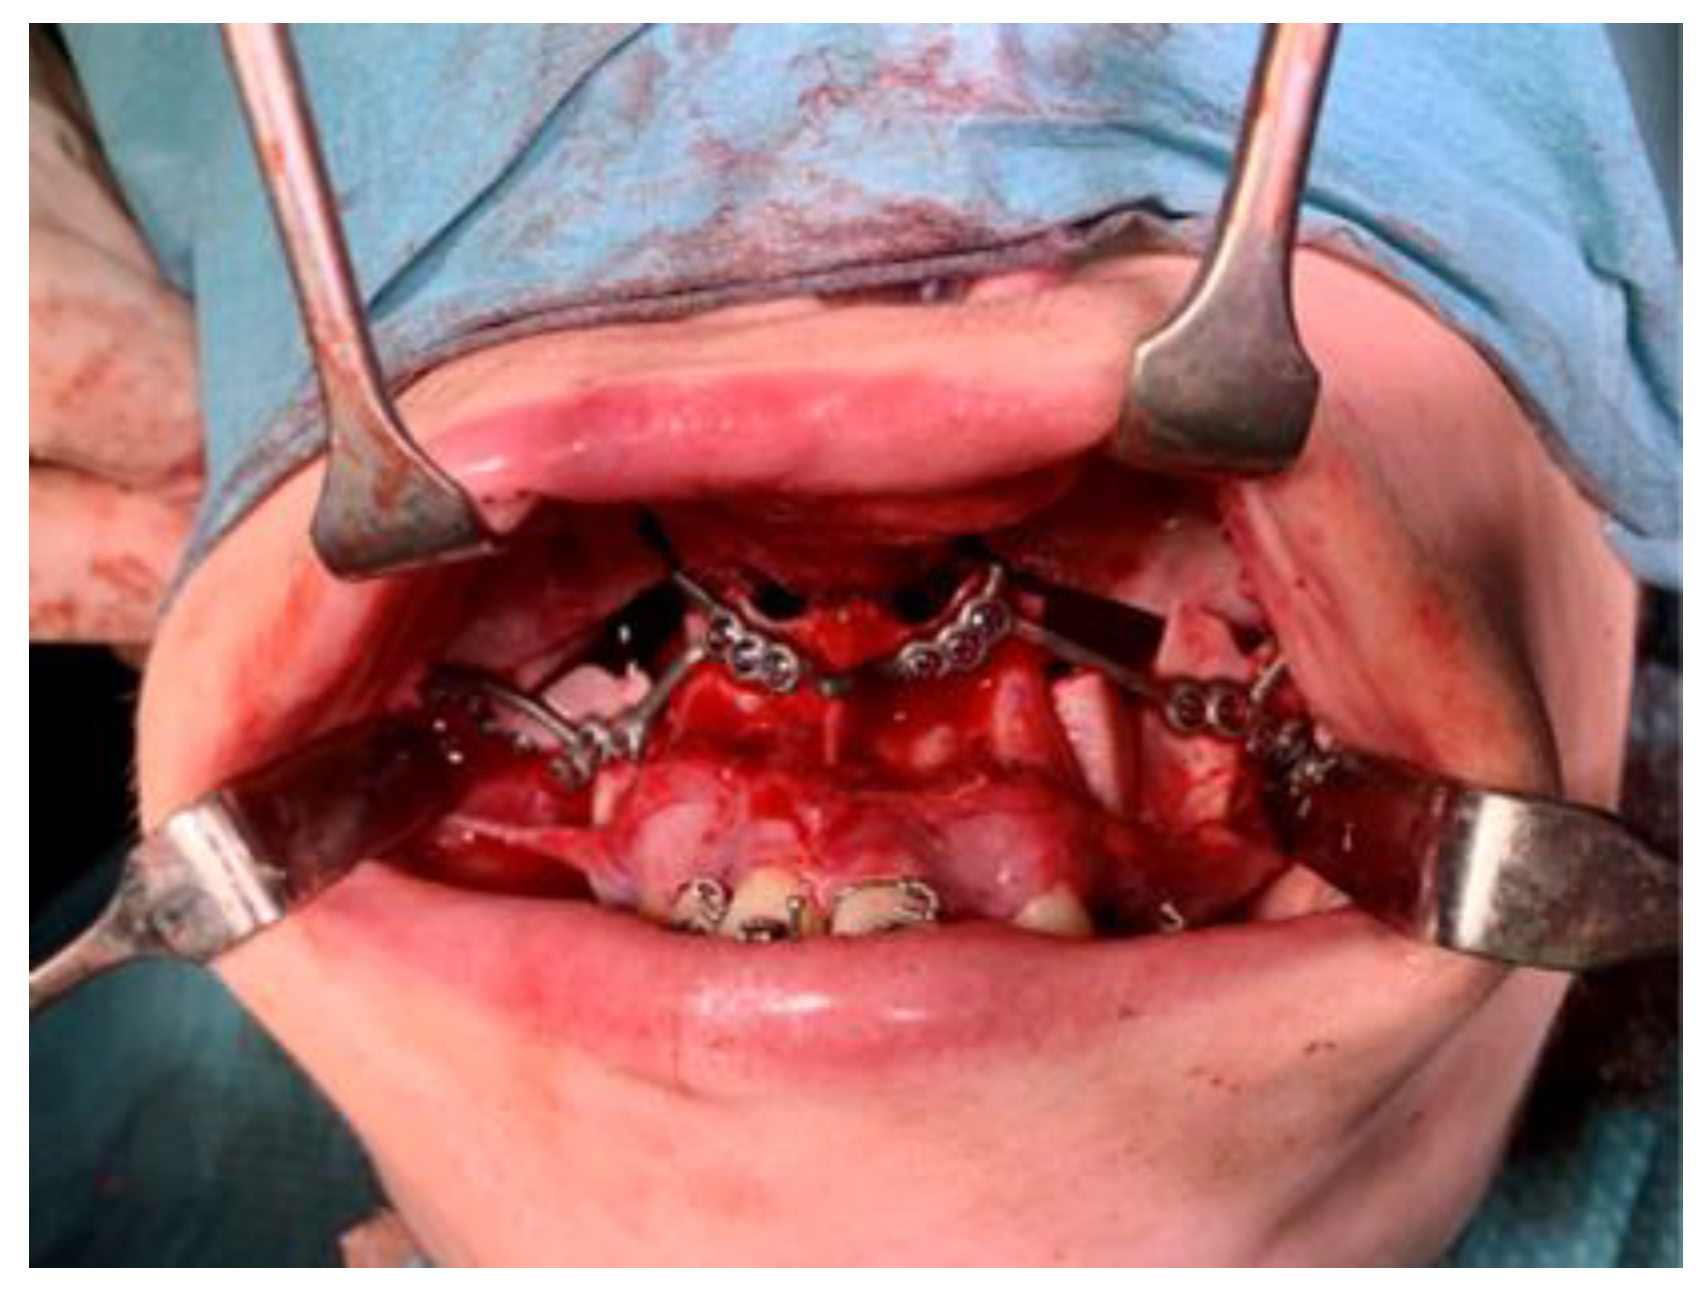

2.3.1. Mandible

2.3.2. Maxilla